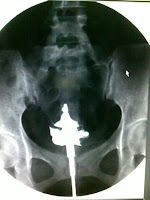

KRITERIA RADIOGRAFI PEMERIKSAAN HSG SET :

- Bentuk dari uterus yang normal berbentuk segitiga, bagian dasarnya pada fundus dan apex pada sisi inferior, berhubungan dengan canalis cervikalis.

- Tidak ada gambaran kelainan seperti tumor, polip, atau bentuk abnormal dari uterus.

- Tuba fallopi terletak di kanan kiri uterus. Terbagi atas empat daerah yaitu: interstitial, isthmus, ampulla dan infundibulum. Daerah yang terlihat jelas dengan kontras adalah isthmus yang panjang dan lurus serta ampulla yang seperti huruf “s” dan tampak melebar. Tuba fallopi tidak tersumbat, sehingga media kontras dapat mengisi tuba hingga tumpah ke rongga peritoneal (tampak spil) .

- Terdapat gambaran spekulum maupun partubator di rongga uterus pada metode pemasukan media kontras dengan metal canula .